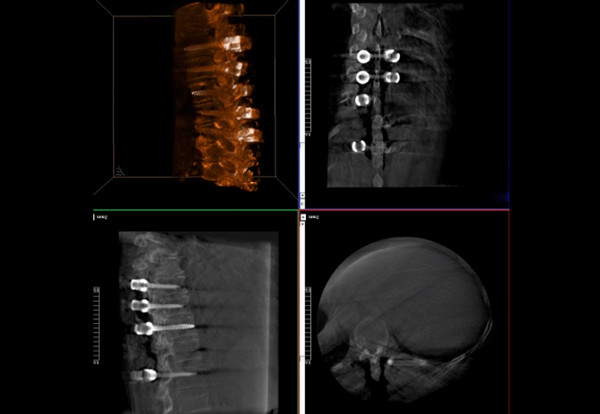

普愛醫(yī)療術(shù)中三維導(dǎo)航C臂快速生成橫斷面、矢狀面、冠狀面斷層圖像和三維立體圖像,方便醫(yī)生確認(rèn)手術(shù)部位。C形臂的大平板帶來(lái)出色的顯示視野,可以更好的顯示手術(shù)部位全局情況,確保手術(shù)規(guī)劃及執(zhí)行的準(zhǔn)確性。

三維影像檢驗(yàn)螺釘植入效果

一臺(tái)C形臂

二維三維影像 皆能完好呈現(xiàn)